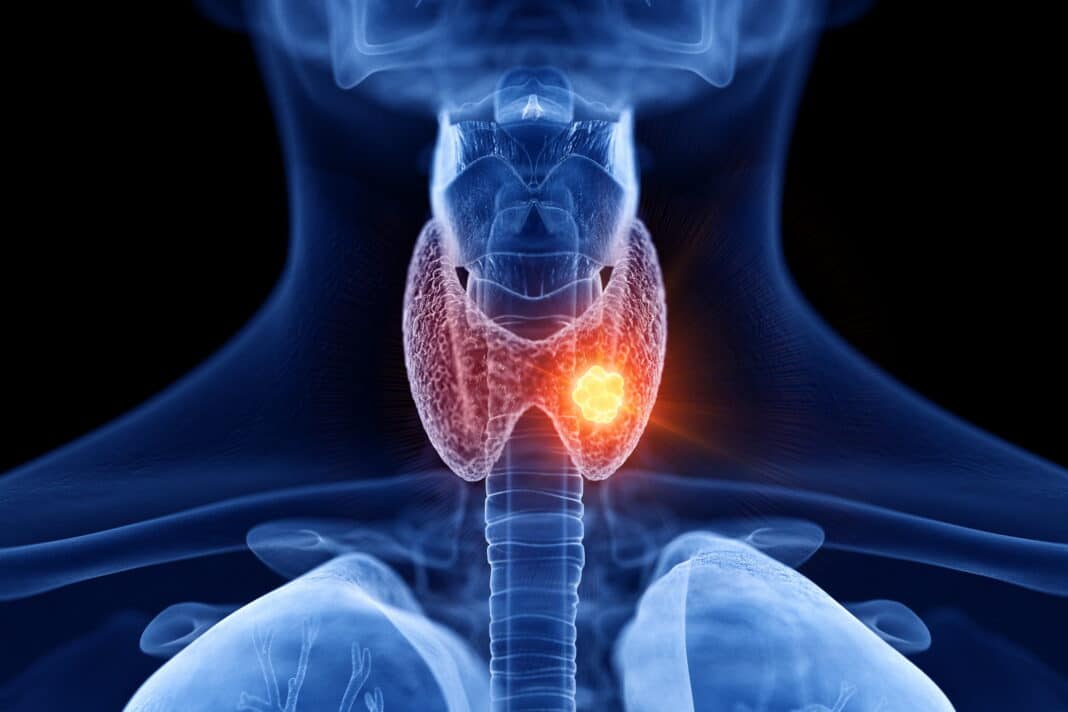

Ο καρκίνος μπορεί να χτυπήσει σε οποιαδήποτε ηλικία και φύλο. Ένας από τους πιο συνηθισμένους τύπους της νόσου είναι εκείνος του θυροειδούς. Εμφανίζεται σε ηλικίες 45-54 ετών, αλλά μπορεί να προσβάλλει και οποιαδήποτε άλλη νεότερη ηλικία.

Περίπου το 1,2% των ανδρών και των γυναικών έχει πιθανότητα να αντιμετωπίσουν αυτήν την κακοήθεια κάποια στιγμή στη ζωή τους.

Καρκίνος του θυροειδούς: 4 παράγοντες που αυξάνουν τον κίνδυνο